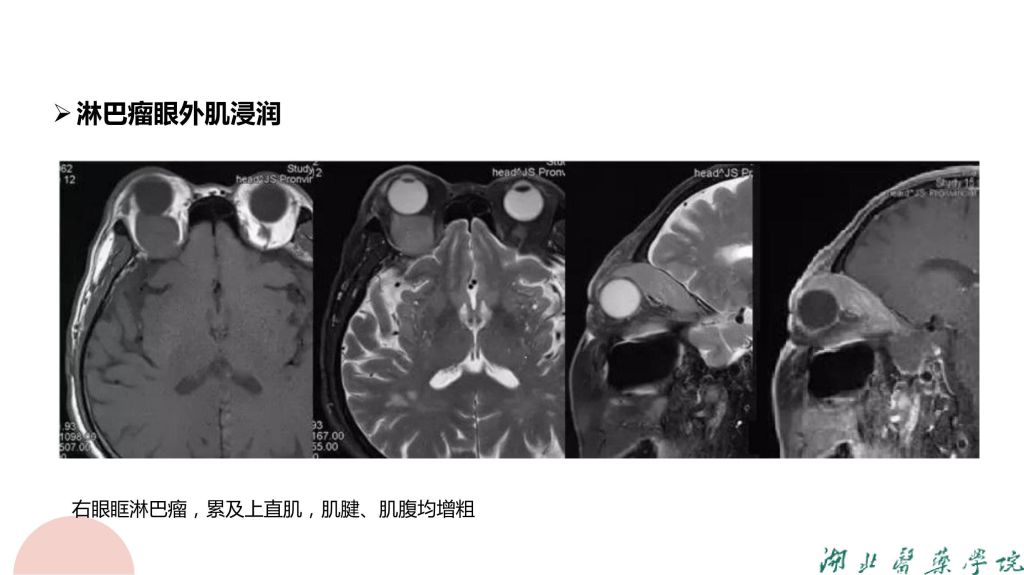

病例分析-眼眶淋巴瘤